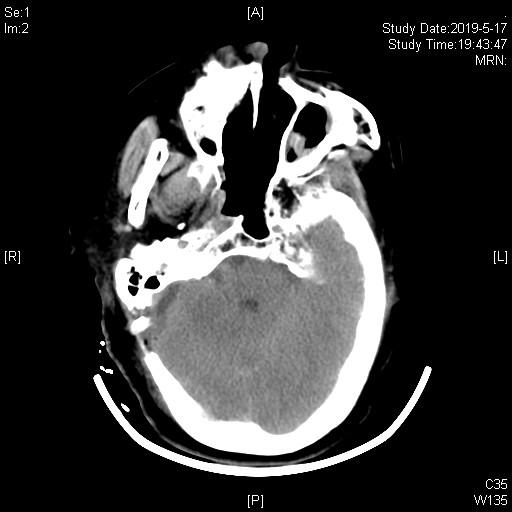

术后复查CT术区无出血,患者手术后立即停跳。